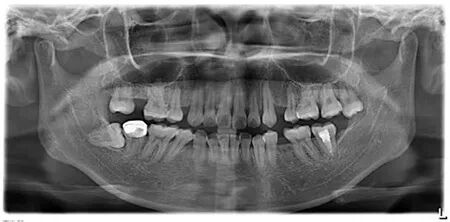

曲面平展片在一般门诊或医院也都可以拍到,它的优点是可以展现出整个口腔里的牙齿,及口腔周边解剖结构颌骨,但缺点在于图片上的牙齿容易失真。

曲面断层片一般用于全口牙齿的检查及颌骨的检查,相对小牙片的龋病检查,曲面断层片更适用于检查智齿的生长情况,种植牙的术前检查等等。